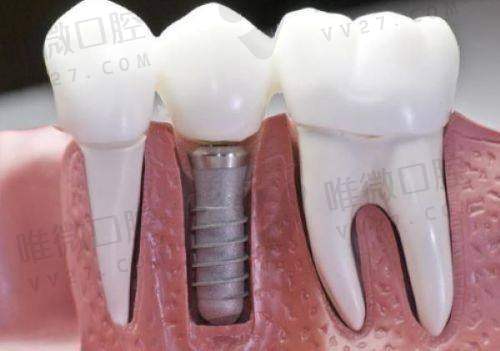

种植牙、牙齿矫正、牙周治疗、全瓷牙修复、牙体牙髓病治疗

拜伦口腔是国内连锁牙科品牌,在多个城市设有分支机构,罗定店作为其布局中的一环,秉持统一医疗标准。该店设有夜诊服务,便于上班族和学生错峰就诊。具备CBCT影像系统、种植导航设备,提升治疗的可视化和精细度。在种植牙领域有All-on-4、穿颧种植等精良方案。